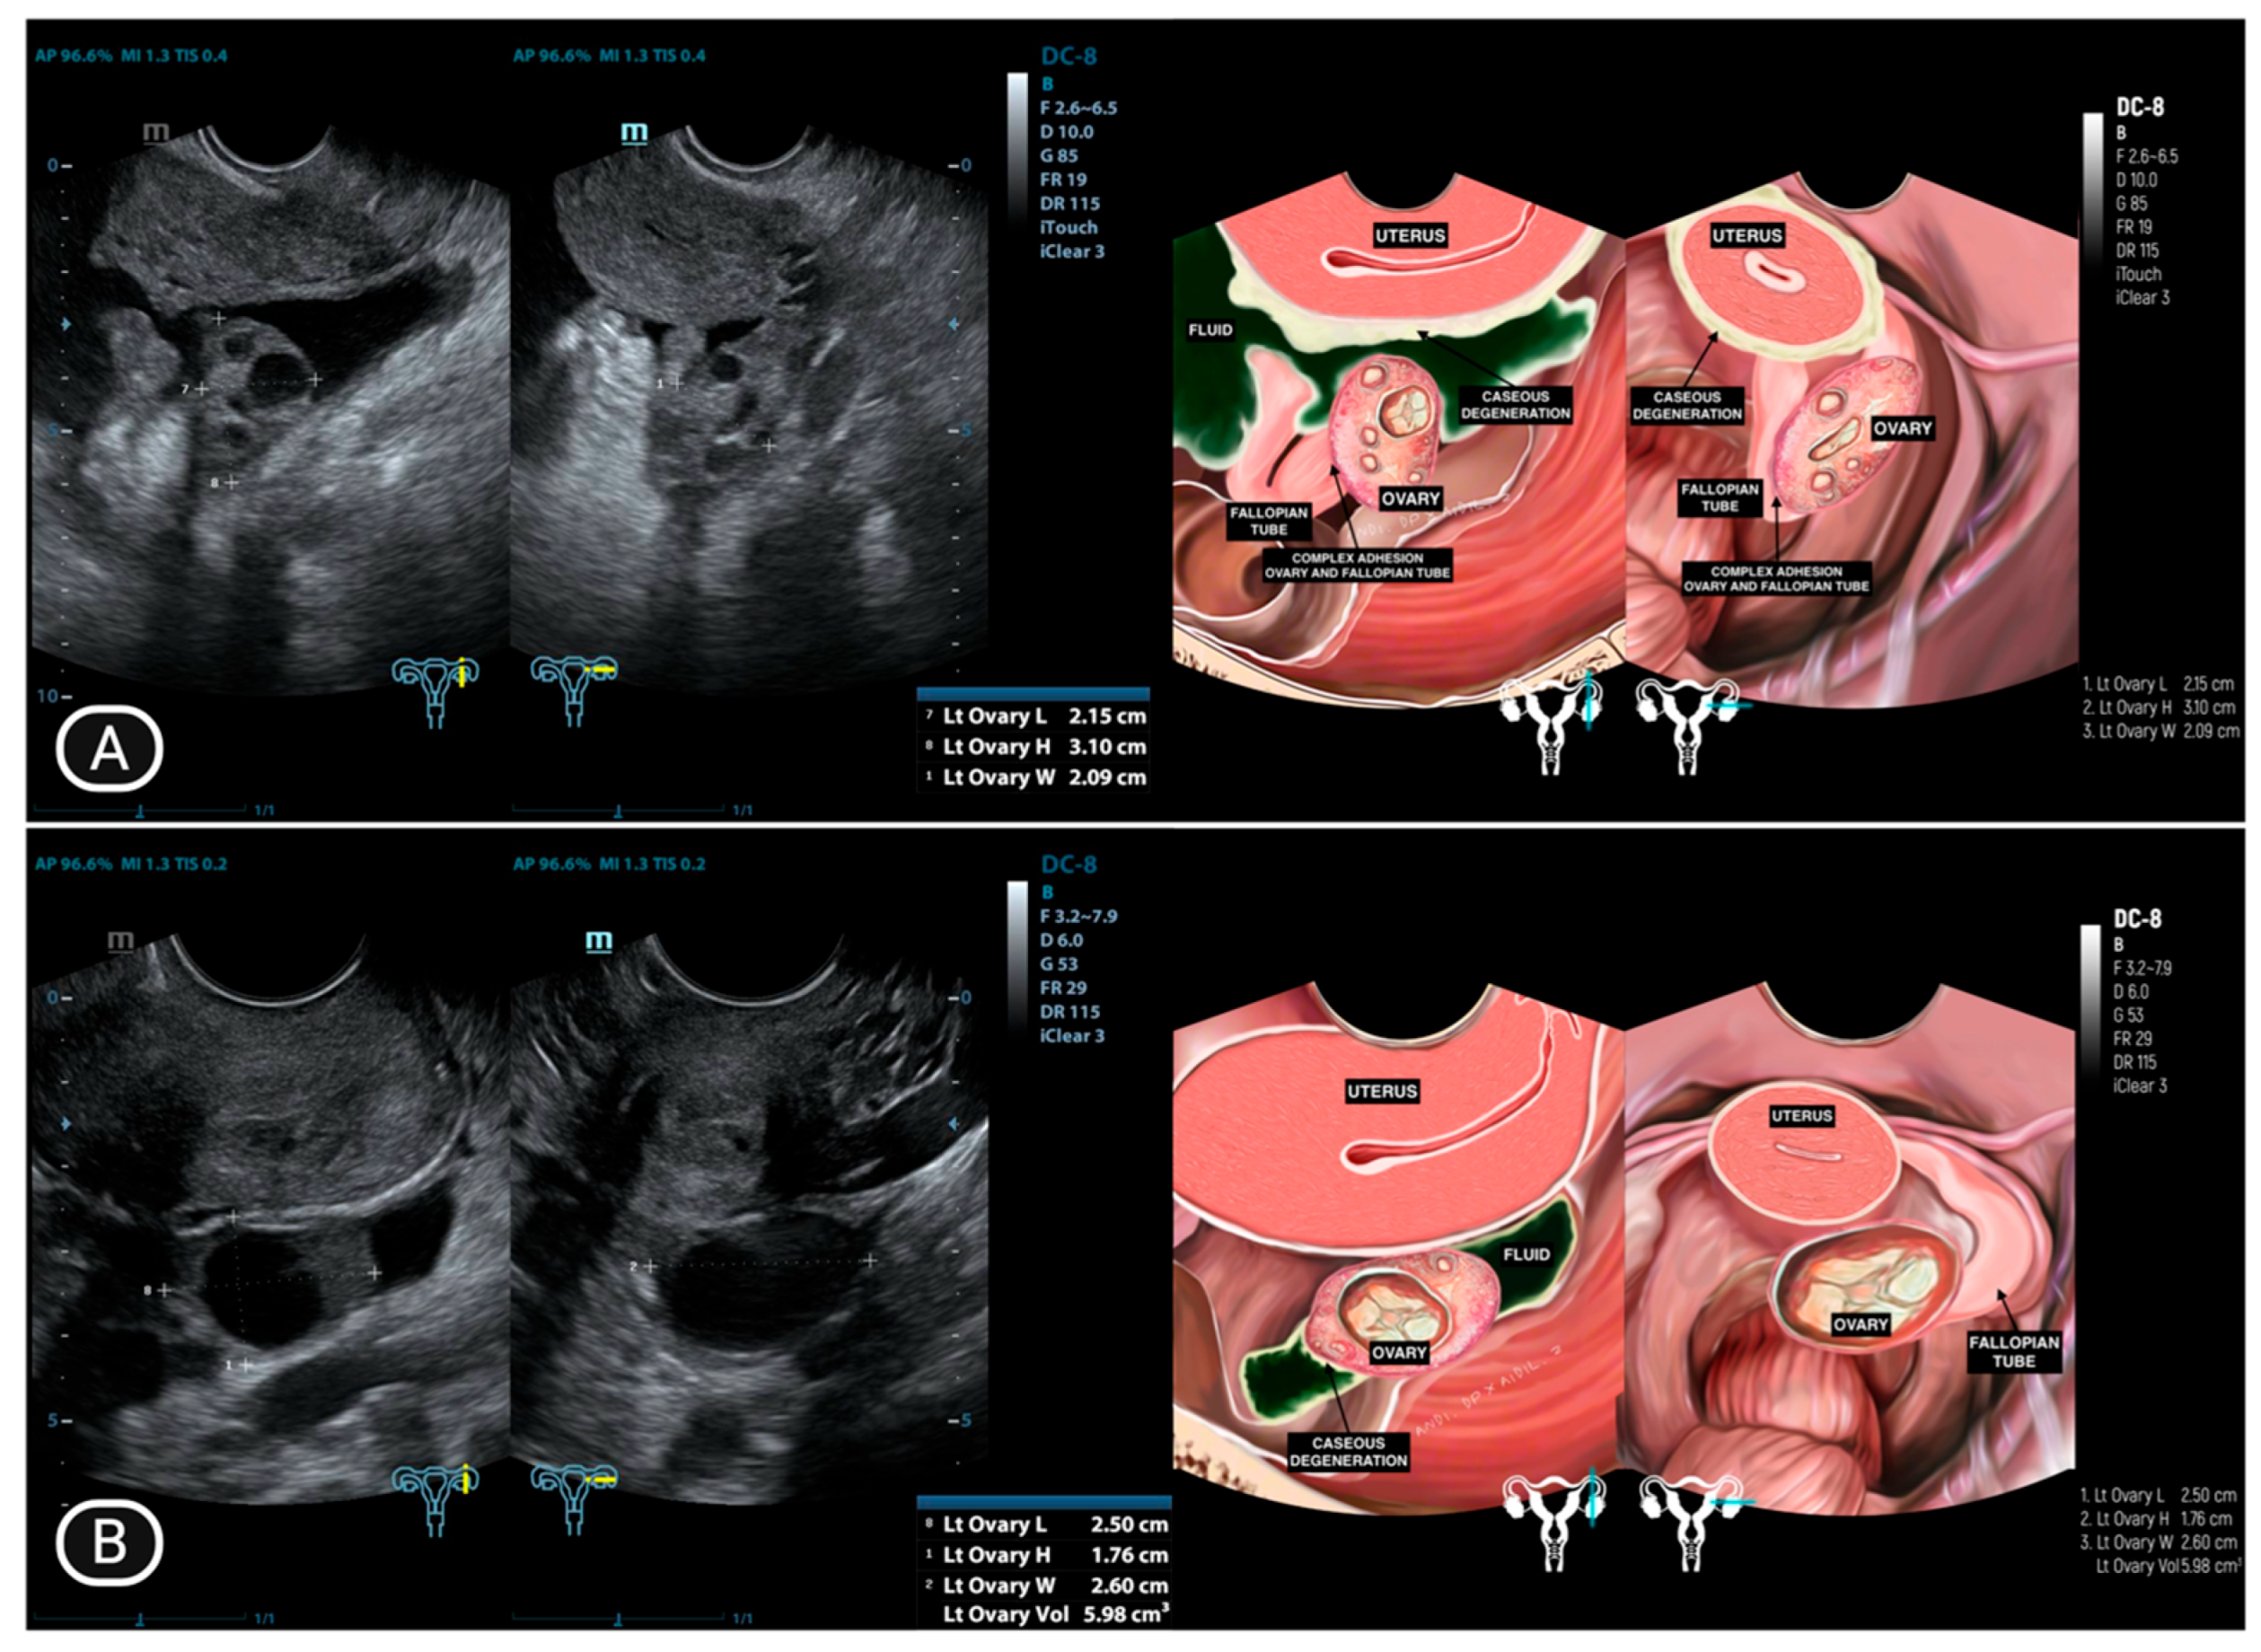

| 1 | LA (25) | Normal | Adhesion complex with hydrosalpinx right fallopian tube | Hydrosalpinx, filled with caseous degeneration inside | Adhesion complex with hydrosalpinx left fallopian tube | Hydrosalpinx, filled with complex fluid | Complex ascites | (−) |

| 10 | AS (44) * | Ill−defined mass at the anterior | Adhesion complex with hydrosalpinx right fallopian tube | Hydrosalpinx | Enlarged with multilocular cystic filled with complex fluid | Not visualized | (−) | (−) |

| 11 | Y (30) * | Normal | Adhesion to pelvic wall | Not visualized | Adhesion complex with left fallopian tube | Hydrosalpinx, filled with caseous degeneration inside | Complex ascites | (−) |